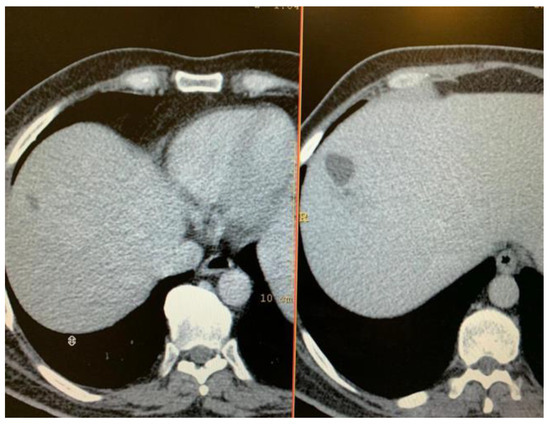

Magnetic resonance imaging (MRI) exam showed deformed right eyeball of reduced volume, with irregulated contour at the level of the medial convexity, at which level the scleral contour appeared interrupted, with underlying thickened choroid and vitreous body prolapse. Posterior lens luxation and increased hematogenous density of vitreous body were evidenced. Moderate inflammation of the preseptal and postseptal soft tissue was noticed (Figure 3).

Figure 3.

MRI exam: Right eye endophthalmitis with scleral abscess and perforation; increased density of vitreous body, deformed eye contour, with 2 area of scleral perforation in the superior and internal part; exophthalmia with inflammatory changes of the periorbital soft tissue.